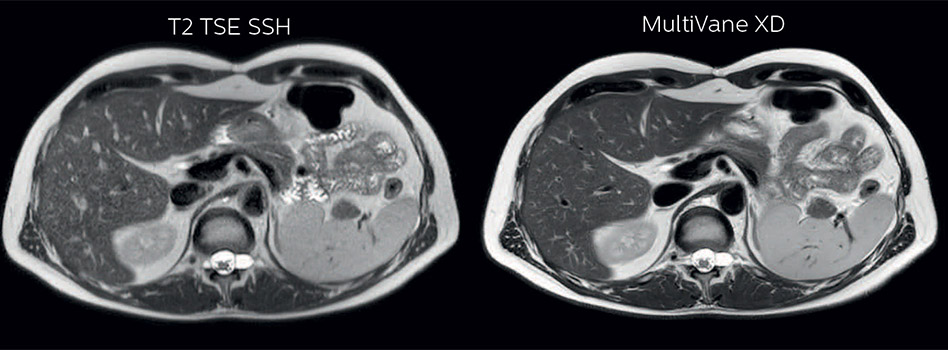

Comparison of liver MRI with and without MultiVane XD motion correction

In this example the image quality of the MultiVane XD images is evidently better than in the images without MultiVane XD. Ingenia 1.5T with dS Torso coil solution.

“I would absolutely recommend to other sites to implement MultiVane XD with dS SENSE in their abdominal cases, as it’s brilliant for robust, motion-corrected abdominal imaging. It provides us with excellent image quality with high resolution in a short time,” says Dr. Baumann. “I would advise using MultiVane XD for T2 and T2 fat suppressed high quality imaging for almost every liver case.”